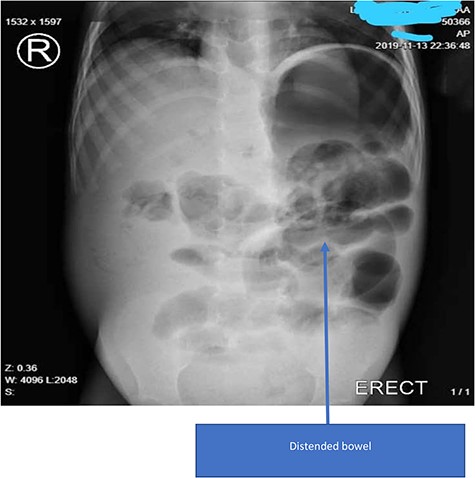

A 3-year-old male of a known Tanzanian nomadic Masaai tribe was brought to the emergency department with a 3-day history of constipation, nonprojectile, bilious vomiting, generalized abdominal distension and pain. His mother denied any history of deworming. His past medical and family history was unremarkable. On physical examination, the child was pale, weak with an altered level of consciousness, Glasgow Coma Score of 12/15 and febrile with a body temperature of 37.9°C. His blood pressure was 112/70 mm Hg with a pulse rate of 90 beats/min. The patient’s abdomen was distended and tender with guarding and dullness to percussion. Laboratory investigations revealed hemoglobin of 9.2 g/dl (12.0–16.0) with normal white blood cells. A plain abdominal X-ray revealed marked gaseous distension of the stomach and bowels without air-fluid levels (Fig. 1). Similar findings were observed in the abdominal ultrasound scan.

Plain X-ray of the patient showing gastrointestinal distention without air-fluid levels or ‘railway tracks’.